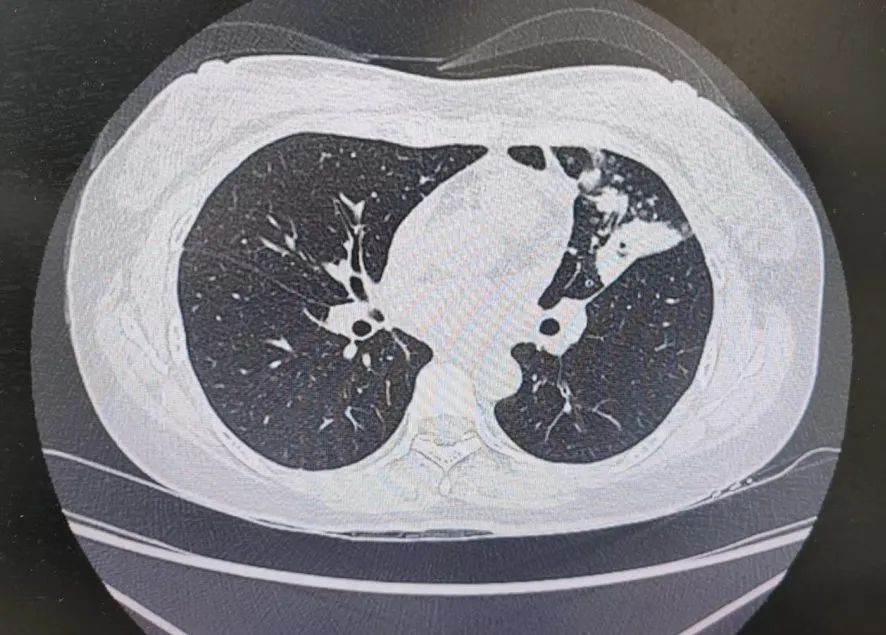

患者肺部CT影像

“一般来说,肺炎经过一周的抗感染治疗,病灶会有所吸收。但陈女士的肺部阴影纹丝不动,这种情况必须提高警惕。”宋刚主任团队立即启动了更深入的“三部精准诊断”程序:

1、支气管镜探查:快速排除气道新生物;

2、肿瘤标志物追踪:多项血清指标显著升高,直指肿瘤可能;

3、CT引导下穿刺活检:病理诊断为左肺上叶腺癌。

肺炎型肺癌,因其影像学表现与普通肺炎极为相似,临床上误诊率极高。然而确诊仅是第一步。宋刚主任当天即召集肿瘤科、病理科、影像科等多学科专家会诊,为陈女士制定个体化治疗方案。